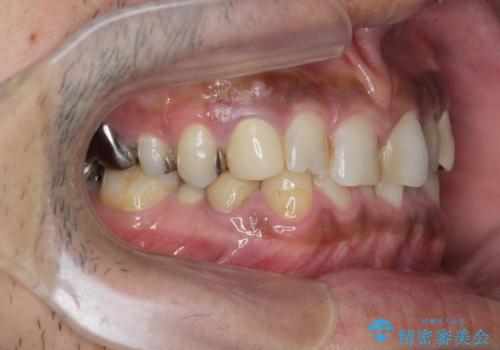

- 長年虫歯の治療を受け続けたことで銀歯・コンポジットレジン修復だらけになってしまい、今後の見た目や歯を大切にするためにセラミック治療矯正治療を希望され来院されました。

マイクロスコープを用いた精密根管治療やセラミック治療、マウスピース矯正治療を一つの医院で行うことのできる当法人ならではの総合歯科治療を実践していきます。

歯並びを整えたことで、歯ブラシのしやすさが向上し見た目も銀歯を全て除去したことで大きく改善して大変満足いただくことができました。